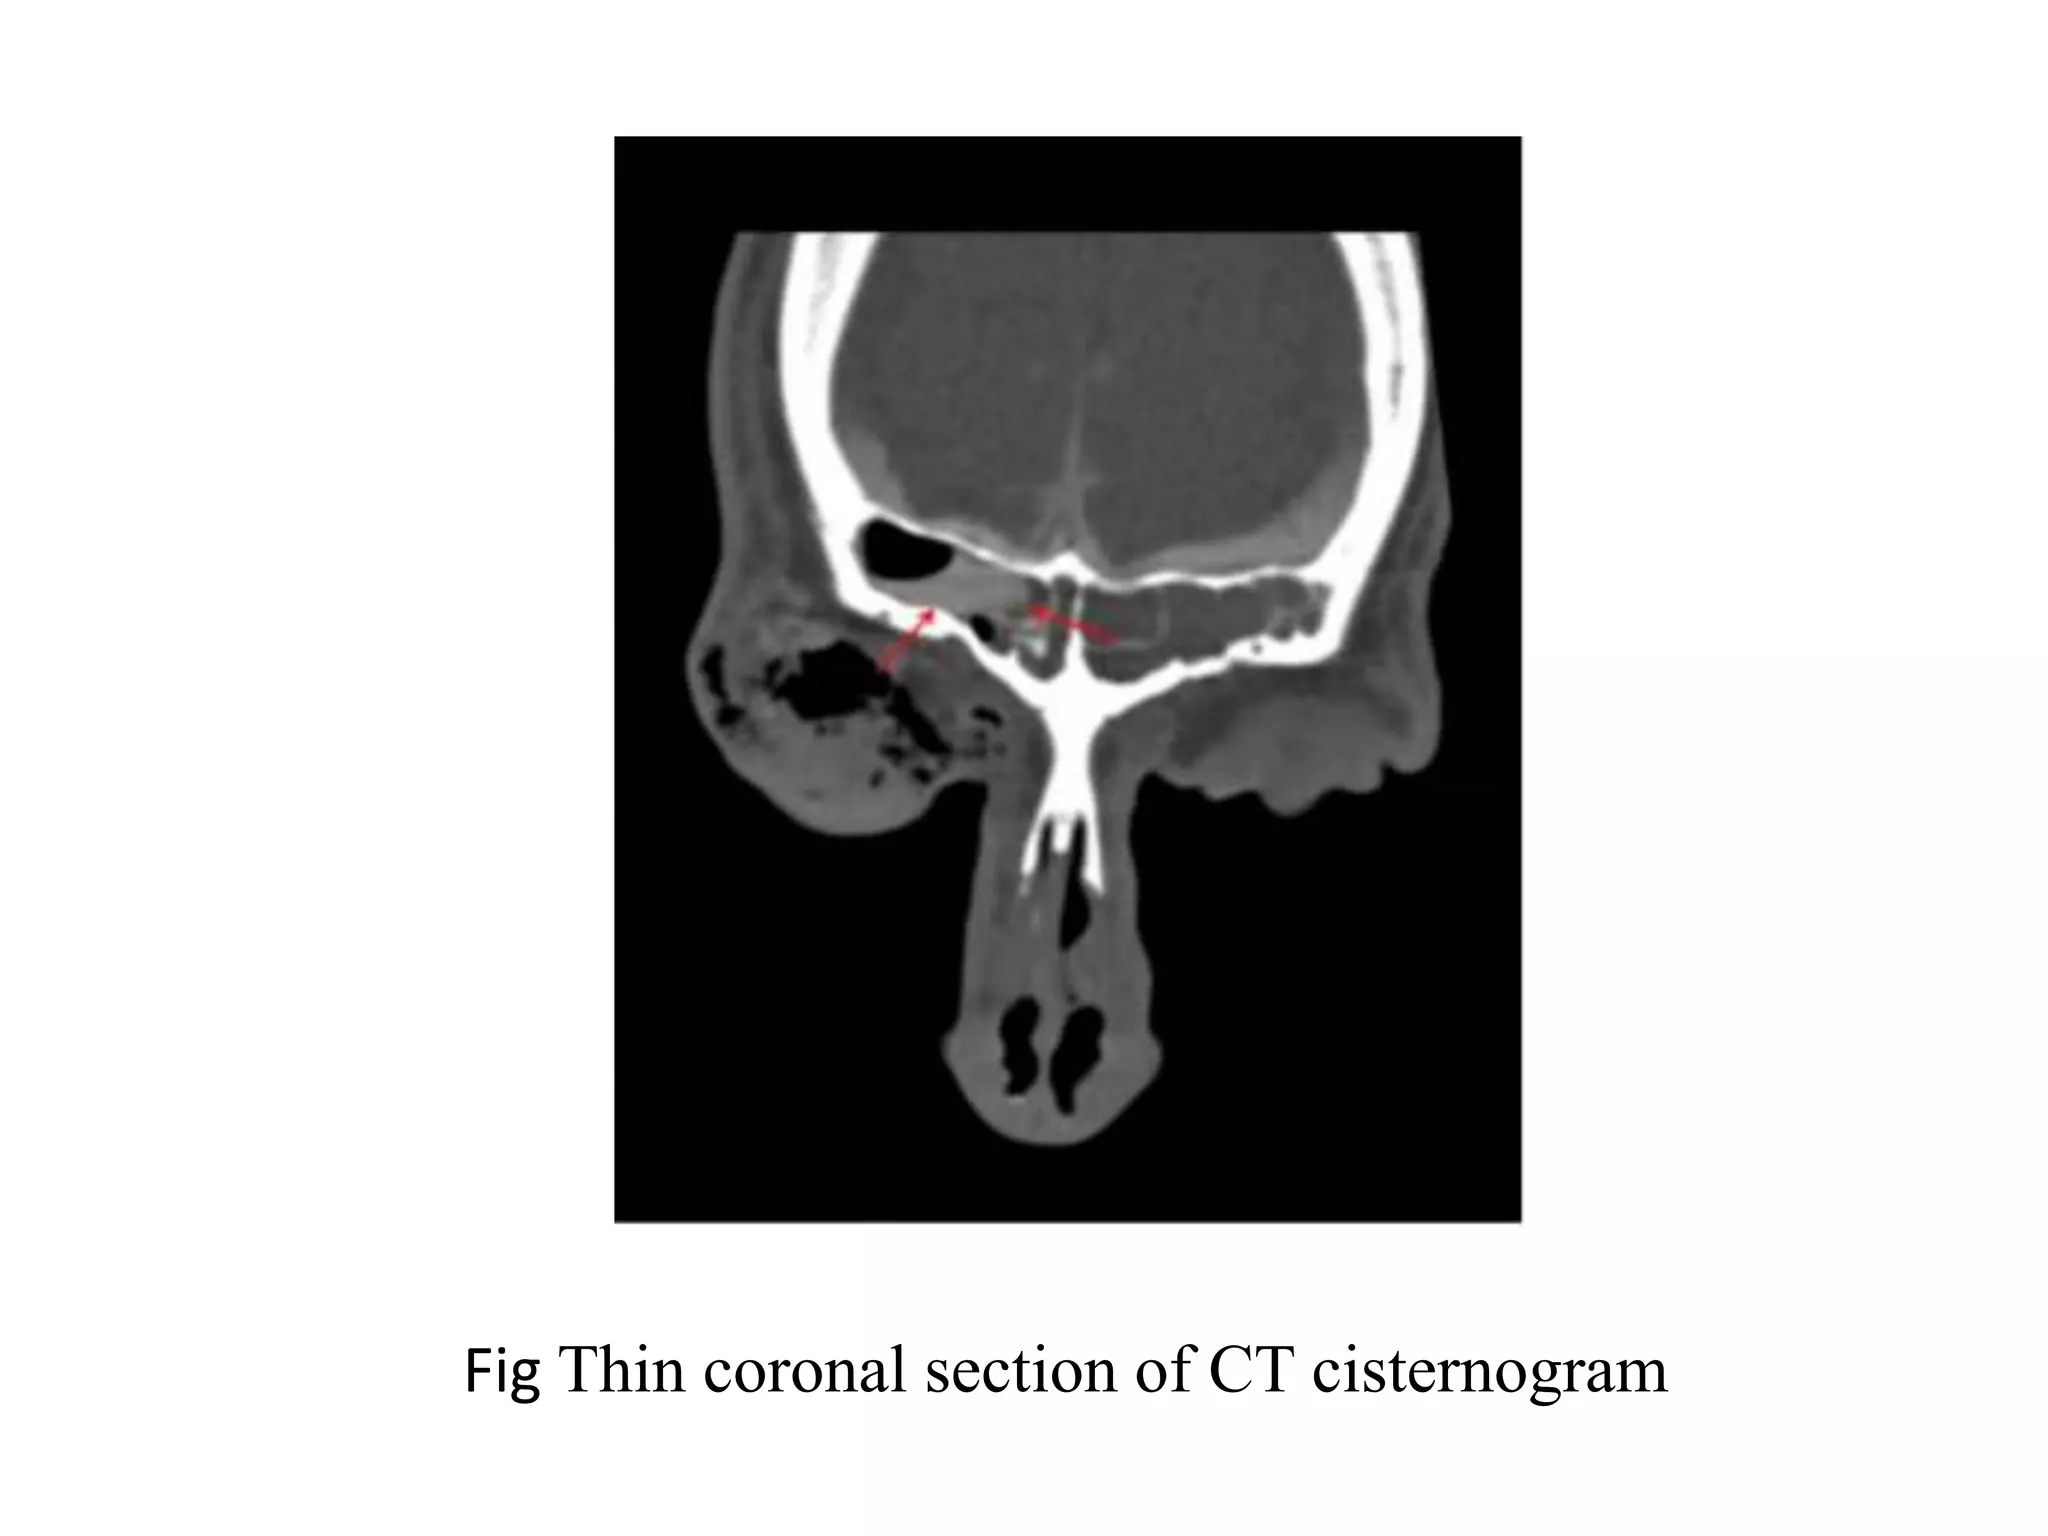

Fig: Thin coronal section of ct cisternogram

Fig Thin coronal section of ct cisternogram